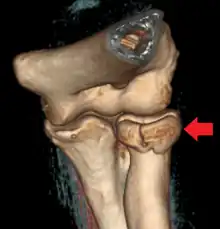

Radial head fracture seen on 3D CT reconstruction